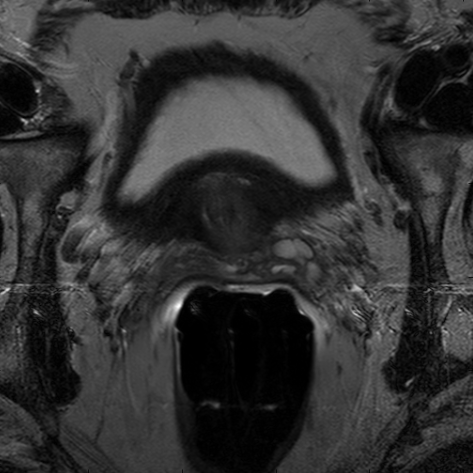

We trained our network on 77 patients. The input images and the manual ground truth annotation are shown in Fig.4. As we have described above, these images were acquired from different patients, and these images include the clinical variability. To evaluate our method, we randomly selected 4 patients with 64 images before training. These images do not take part in training and the prostate has been manually pre-delineated by a radiologist, which were used as the ground truth to evaluate the performance of automatic segmentation. We also selected dice coefficient as the evaluation method[30]. And to validate our method against U-Net and fully convolutional networks (FCNs), we used the same dataset to train and test the U-Net and FCNs.

To intuitively compare the proposed method with U-Net and FCN, the segmentation results of some representative and challenging samples are shown in Fig 5. It can be seen that these prostate images have fuzzy boundaries and the pixel intensity distributions are inhomogeneous both inside and outside of the prostate. Besides, both prostate and nonprostate regions have similar contrast and intensity distributions. All of these phenomenons make the segmentation difficult.